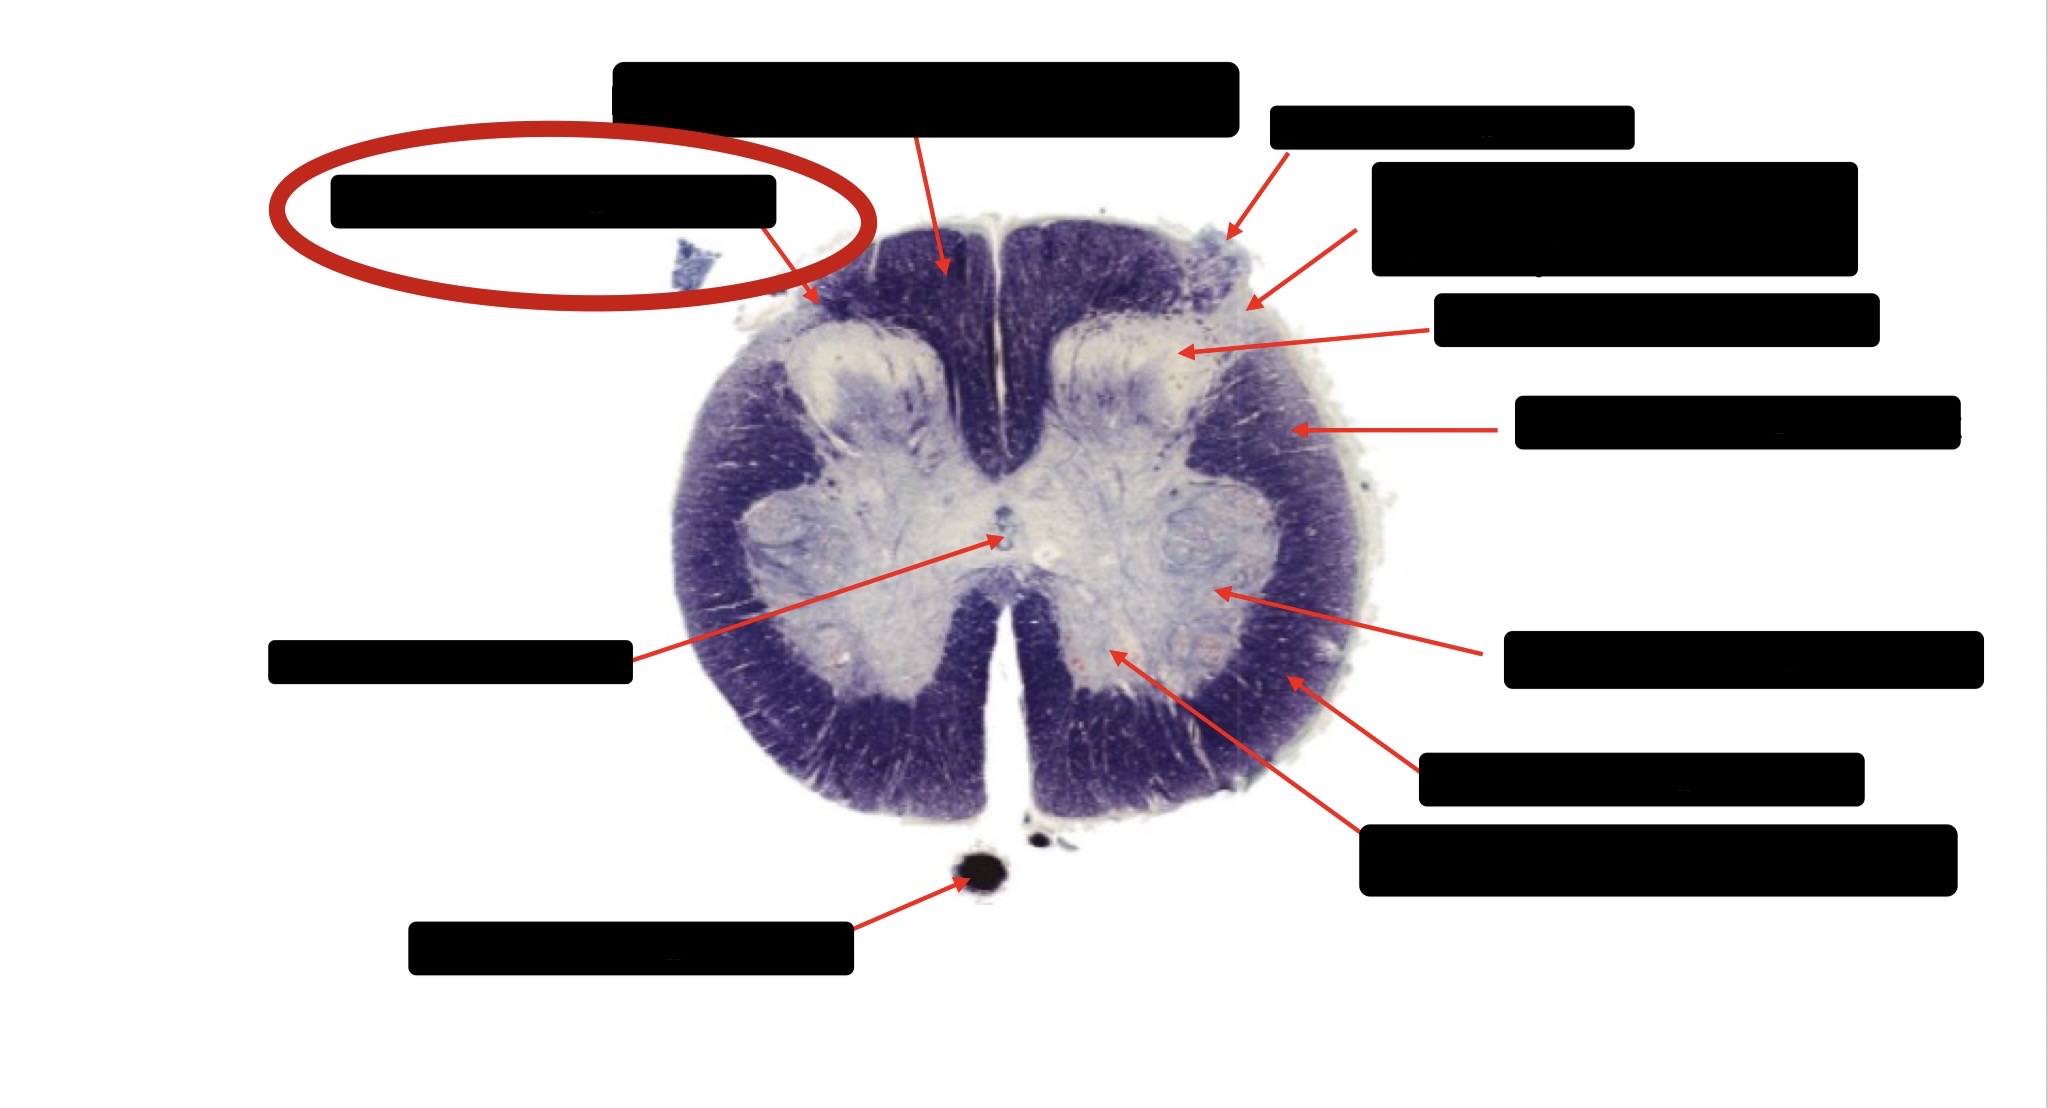

Posterior Column

Large Fiber Entry Zone

Posterior Spinocerebellar Tract

Clarke’s Nucleus

Anterior Spinocerebellar Tract

Ventral Root Fibers

Central Canal

Lissauer’s Tract & Small Fiber Entry Zone

Substantia Gelatinosa

Lateral Corticospinal Tract

Spinothalamic Tract

Anterior Horn Motor Neurons (Distal Muscles)

Anterior Horn Motor Neurons (Proximal Muscles)

Dorsal Rootlet

Lateral Horn

Spinothalmic Tract